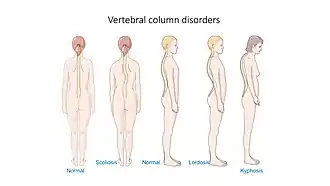

Kyphosis is an abnormally excessive convex curvature of the spine as it occurs in the thoracic and sacral regions.[1][2] Abnormal inward concave lordotic curving of the cervical and lumbar regions of the spine is called lordosis. It can result from degenerative disc disease; developmental abnormalities, most commonly Scheuermann's disease; Copenhagen disease, osteoporosis with compression fractures of the vertebra; multiple myeloma; or trauma. A normal thoracic spine extends from the 1st thoracic to the 12th thoracic vertebra and should have a slight kyphotic angle, ranging from 20° to 45°. When the "roundness" of the upper spine increases past 45° it is called kyphosis or "hyperkyphosis". Scheuermann's kyphosis is the most classic form of hyperkyphosis and is the result of wedged vertebrae that develop during adolescence. The cause is not currently known and the condition appears to be multifactorial and is seen more frequently in males than females.[3]

In the sense of a deformity, it is the pathological curving of the spine, where parts of the spinal column lose some or all of their lordotic profile. This causes a bowing of the back, seen as a slouching posture. Kyphosis is distinguished from scoliosis, a condition in which the spine has a sideways curve.